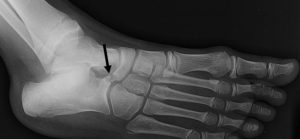

Chez la jeune fille présentant des douleurs chroniques après une entorse le plus souvent bénigne et/ou lorsqu’il s’agit d’un premier épisode, on peut penser à un problème de synostose/synchondrose. Il s’agit d’une fusion ou d’une ankylose d’une articulation. On la retrouve principalement au niveau de la talo-calcanéénne (Figure 4A) et de la calcanéo-naviculaire (Figure 4B).

A l’examen clinique, la douleur est localisée sur le site de la synostose/synchondrose. On retrouve souvent un pied plat valgus peu réductible. Les clichés radiologiques simples permettent de poser le diagnostic en regardant au bon endroit.